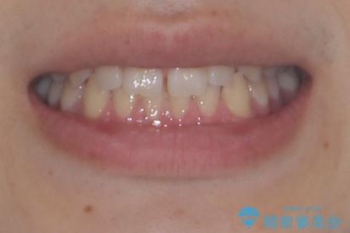

- 「前歯のすきっ歯が気になる」「食べ物が歯の間に詰まりやすい」とのお悩みで来院された20代男性の患者様です。

患者様は「できるだけ目立たない矯正治療」を希望されていたため、インビザラインを用いた治療計画を立案しました。

インビザラインは透明で装着していても気づかれにくく、日常生活やお仕事への影響を最小限に抑えながら治療を進めることが可能です。